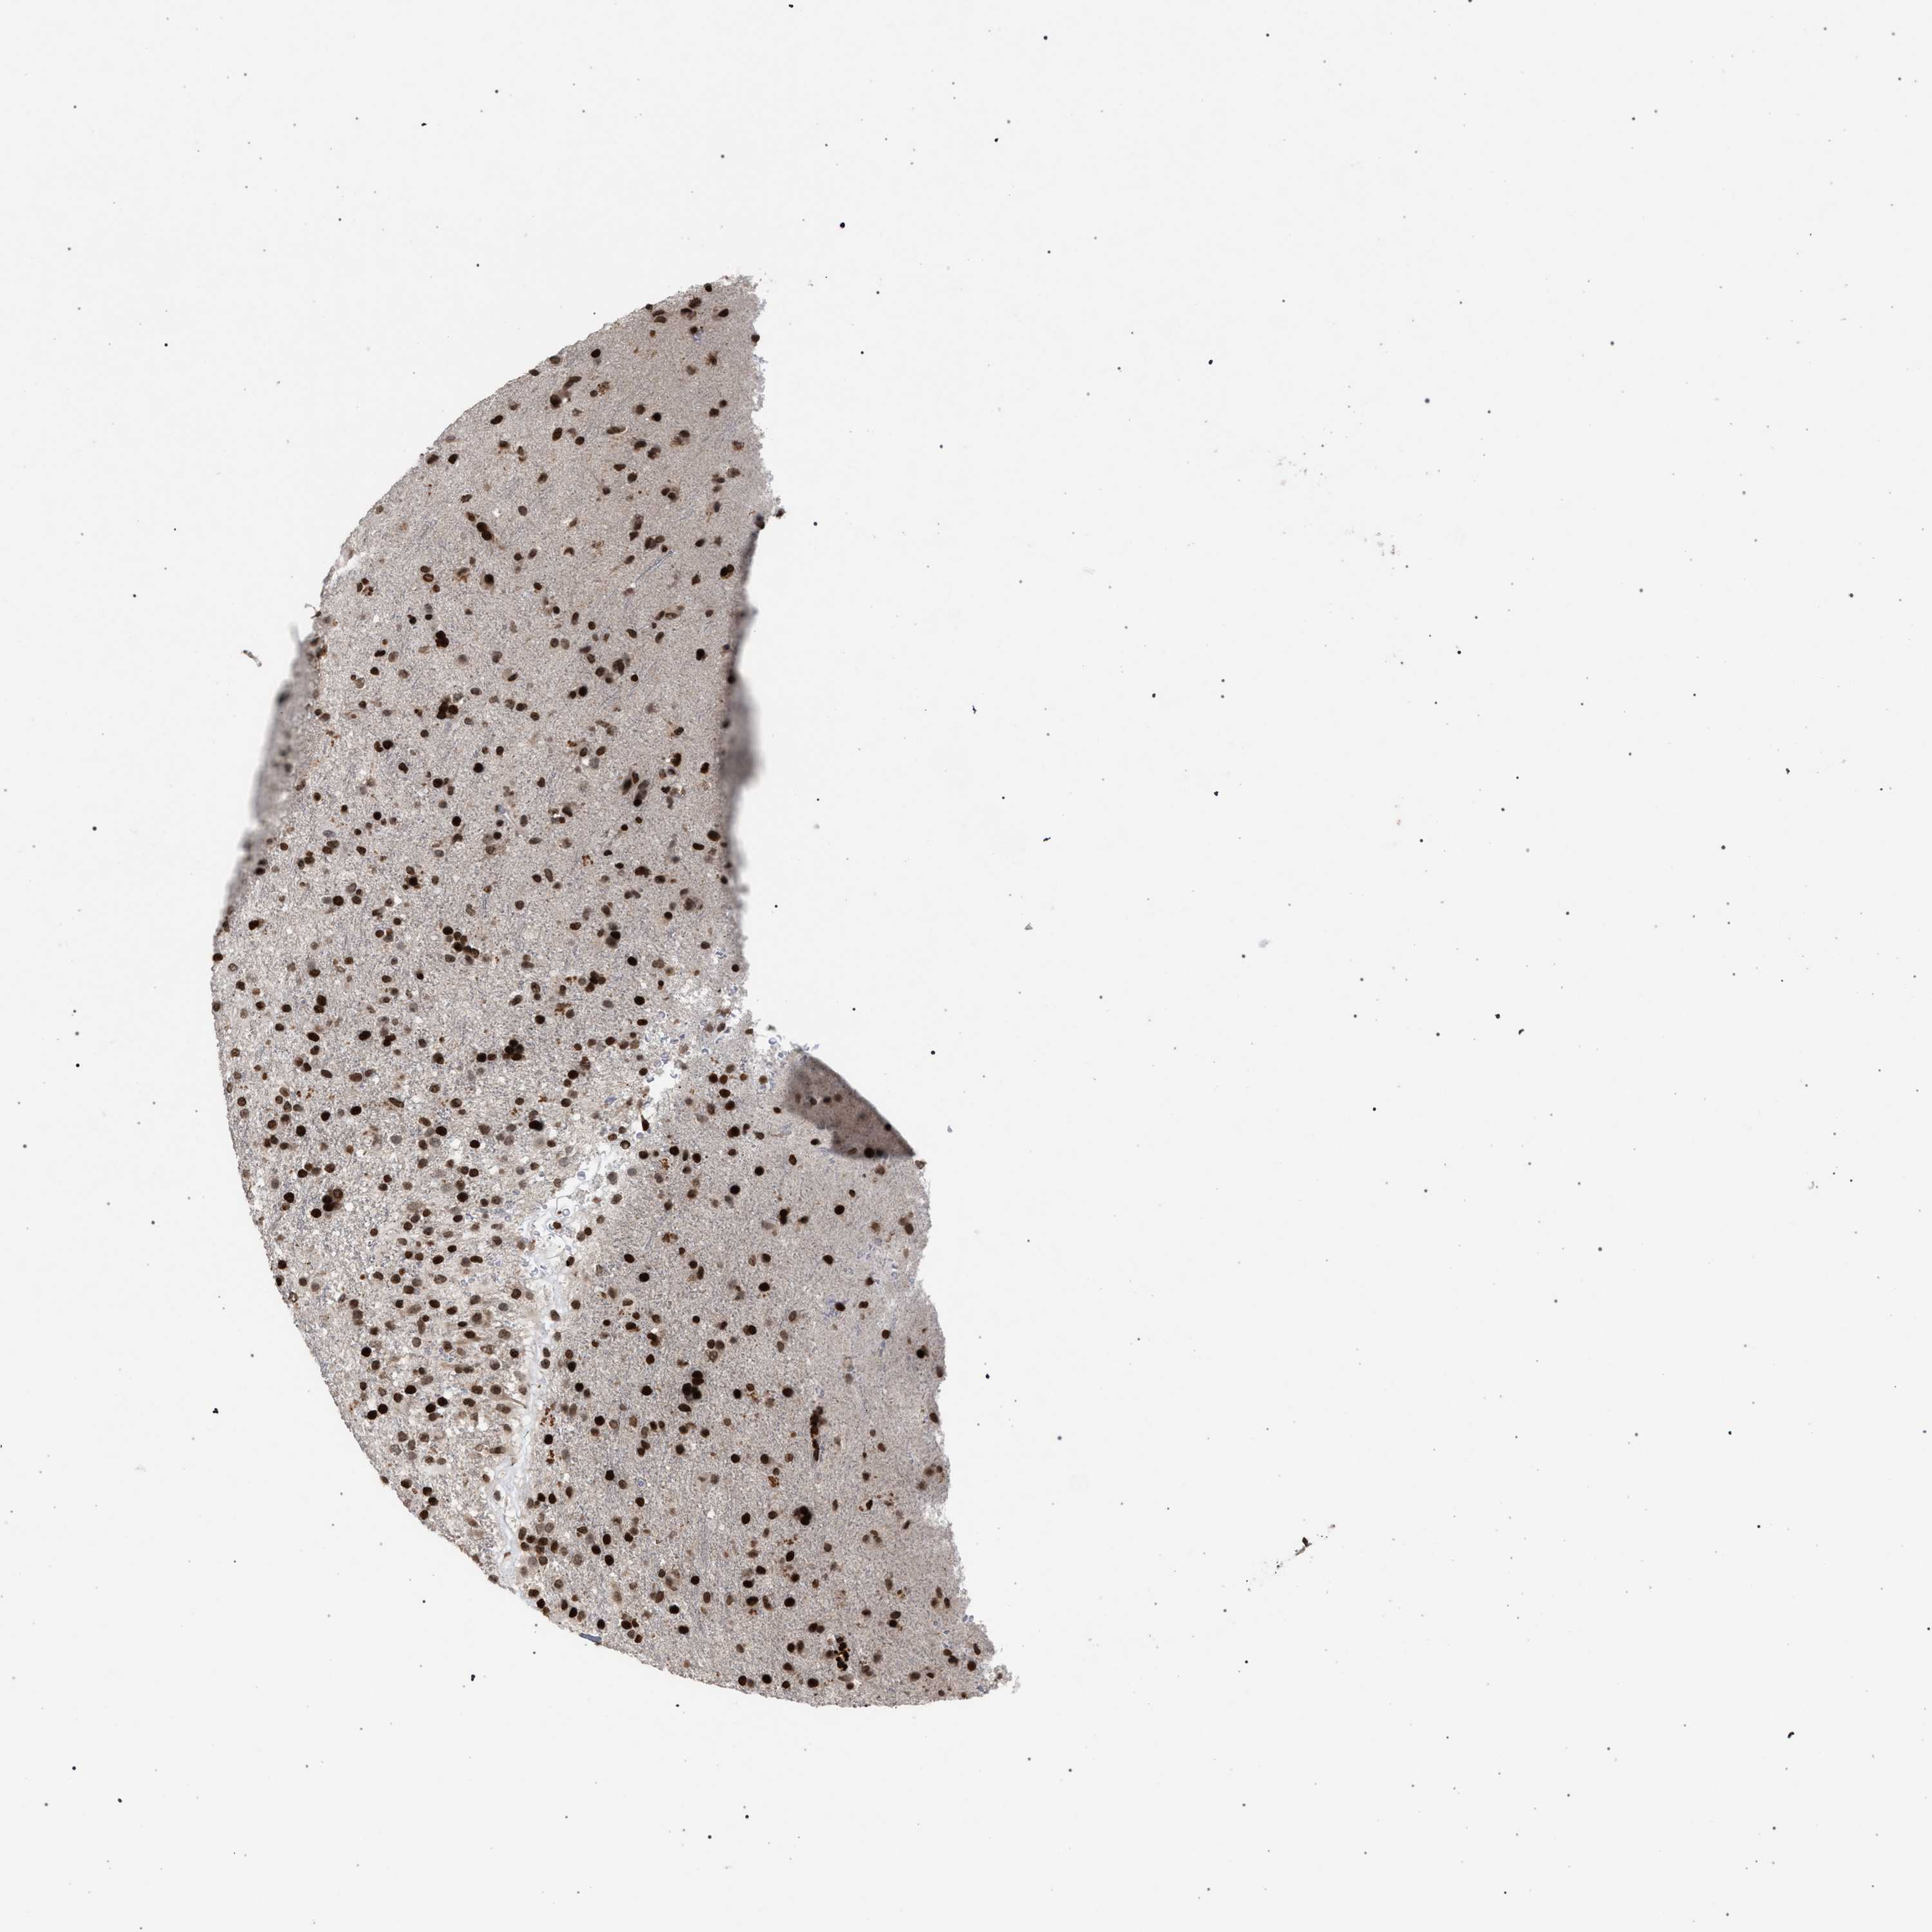

GLIOMA - Protein expressioni

A mouse-over function shows sample information and annotation data. Click on an image to view it in a full screen mode. Samples can be filtered based on level of antibody staining by selecting one or several of the following categories: high, medium, low and not detected. The assay and annotation is described here.

Note that samples used for immunohistochemistry by the Human Protein Atlas do not correspond to samples in the TCGA dataset.

Antibody stainingi

Antibody staining in the annotated cell types in the current human tissue is reported as not detected, low, medium, or high, based on conventional immunohistochemistry profiling in selected tissues. This score is based on the combination of the staining intensity and fraction of stained cells.

Each image is clickable and will lead to virtual microscopy that enables deeper exploration of all samples and also displays staining intensity scores, fraction scores and subcellular localization as well as patient and tissue information for each sample.

Antibody CAB022455

Staining

High

Medium

Low

Not detected

Intensity

Strong

Moderate

Weak

Negative

Quantity

>75%

75%-25%

<25%

None

Location

Nuclear

Cytoplasmic/membranous

Cytoplasmic/membranous,nuclear

Glioma, malignant, High grade

Glioma, malignant, Low grade